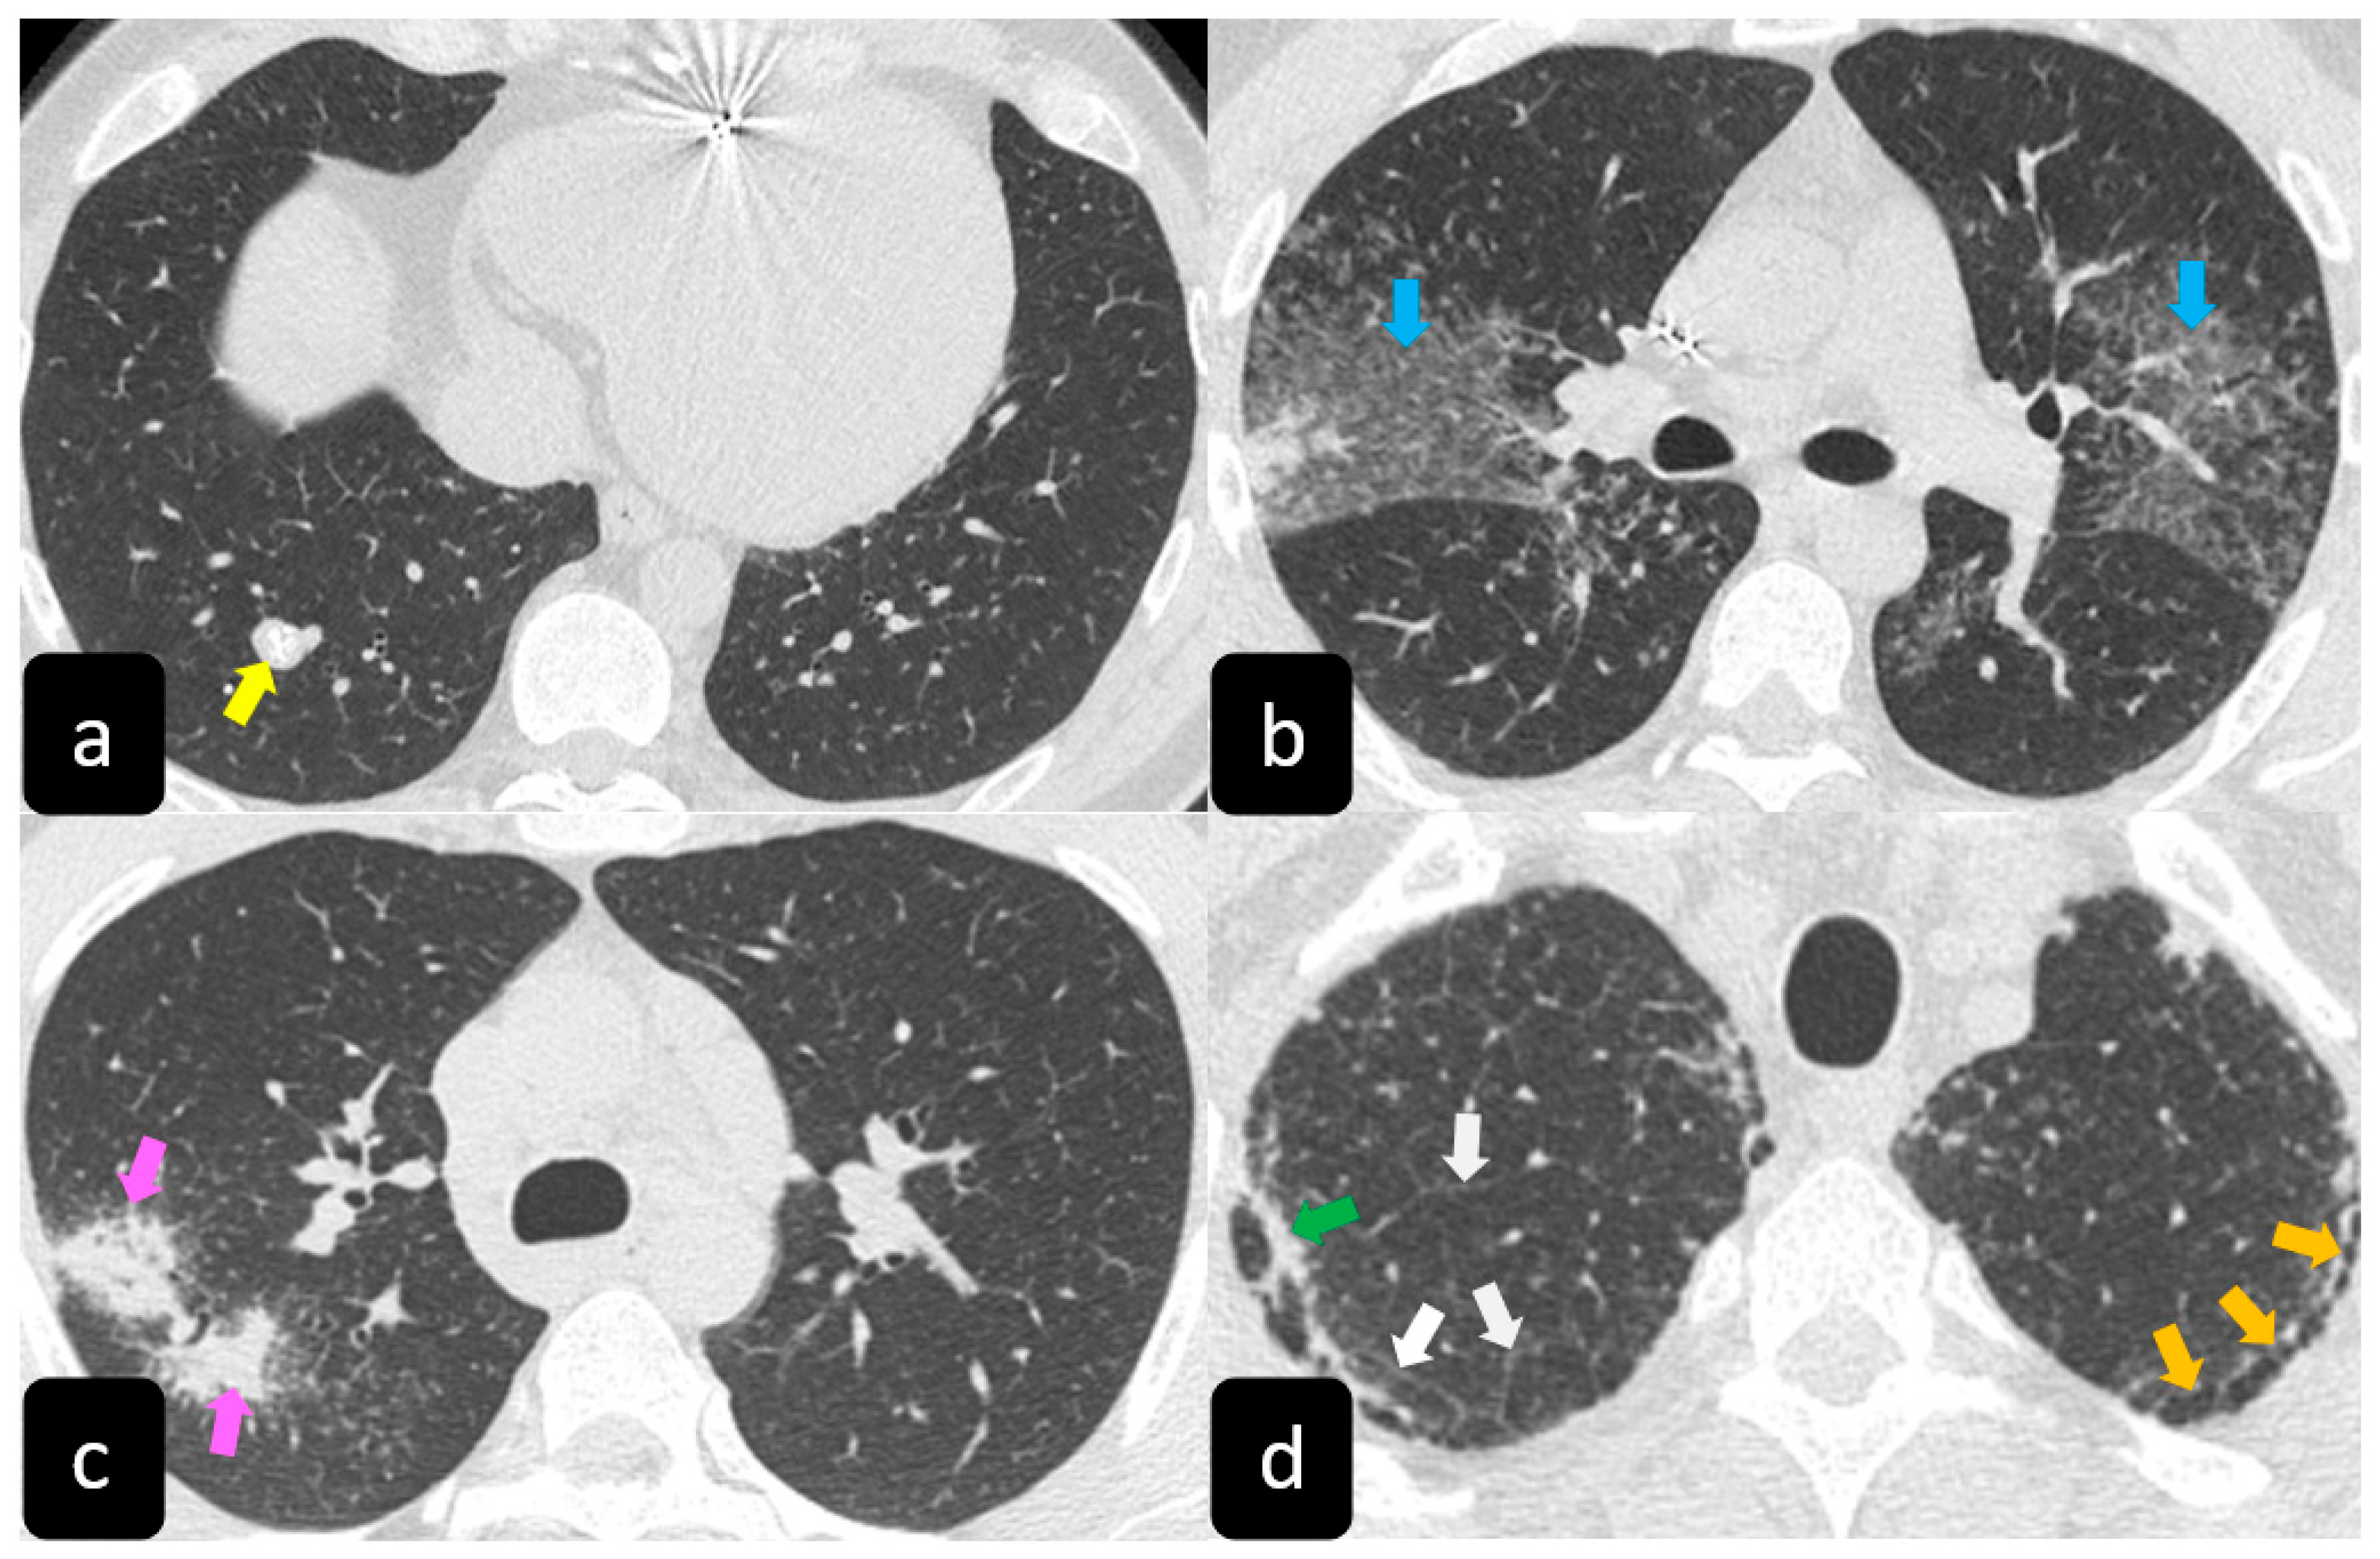

2.2. Typical and Atypical Manifestation of Pulmonary Sarcoidosis at HRCT

3.2. HRCT Findings of Lung Involvement from COVID-19

- Cozzi, D.; Bargagli, E.; Calabrò, A.G.; Torricelli, E.; Giannelli, F.; Cavigli, E.; Miele, V. Atypical HRCT manifestations of pulmonary sarcoidosis. La Radiol. Med. 2018, 123, 174–184. [Google Scholar] [CrossRef]

- Tana, C.; Donatiello, I.; Coppola, M.G.; Ricci, F.; Maccarone, M.T.; Ciarambino, T.; Cipollone, F.; Giamberardino, M.A. CT Findings in Pulmonary and Abdominal Sarcoidosis. Implications for Diagnosis and Classification. J. Clin. Med. 2020, 9, 3028. [Google Scholar] [CrossRef] [PubMed]